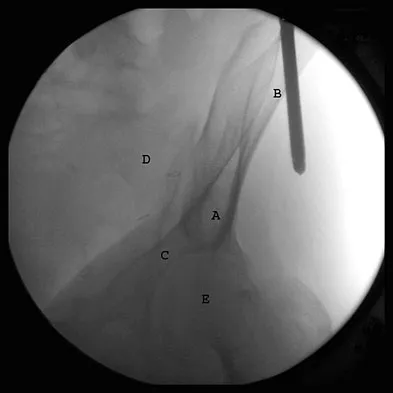

A 12-year-old boy with an ankle fracture undergoes closed reduction under sedation in the emergency department. Figure 27 shows a lateral radiograph of the ankle after two attempts at closed reduction. Based on these findings, treatment should now consist of

Explanation